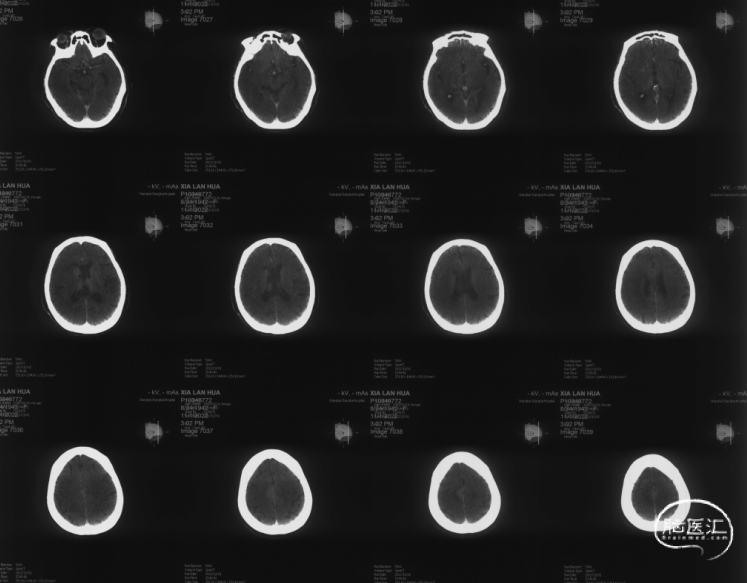

头颅CT平扫:右侧尾状核低密度灶。

ASPECTS:3分

术后即刻Xper-CT扫描:未见颅内出血

术后72h头颅MRI-DWI序列:右侧大脑中动脉供血区弥散受限,轻度脑回增宽、脑沟变浅;中线基本居中。

术后第5天复查脑CTA:右侧颈内动脉、大脑中动脉、大脑前动脉通畅